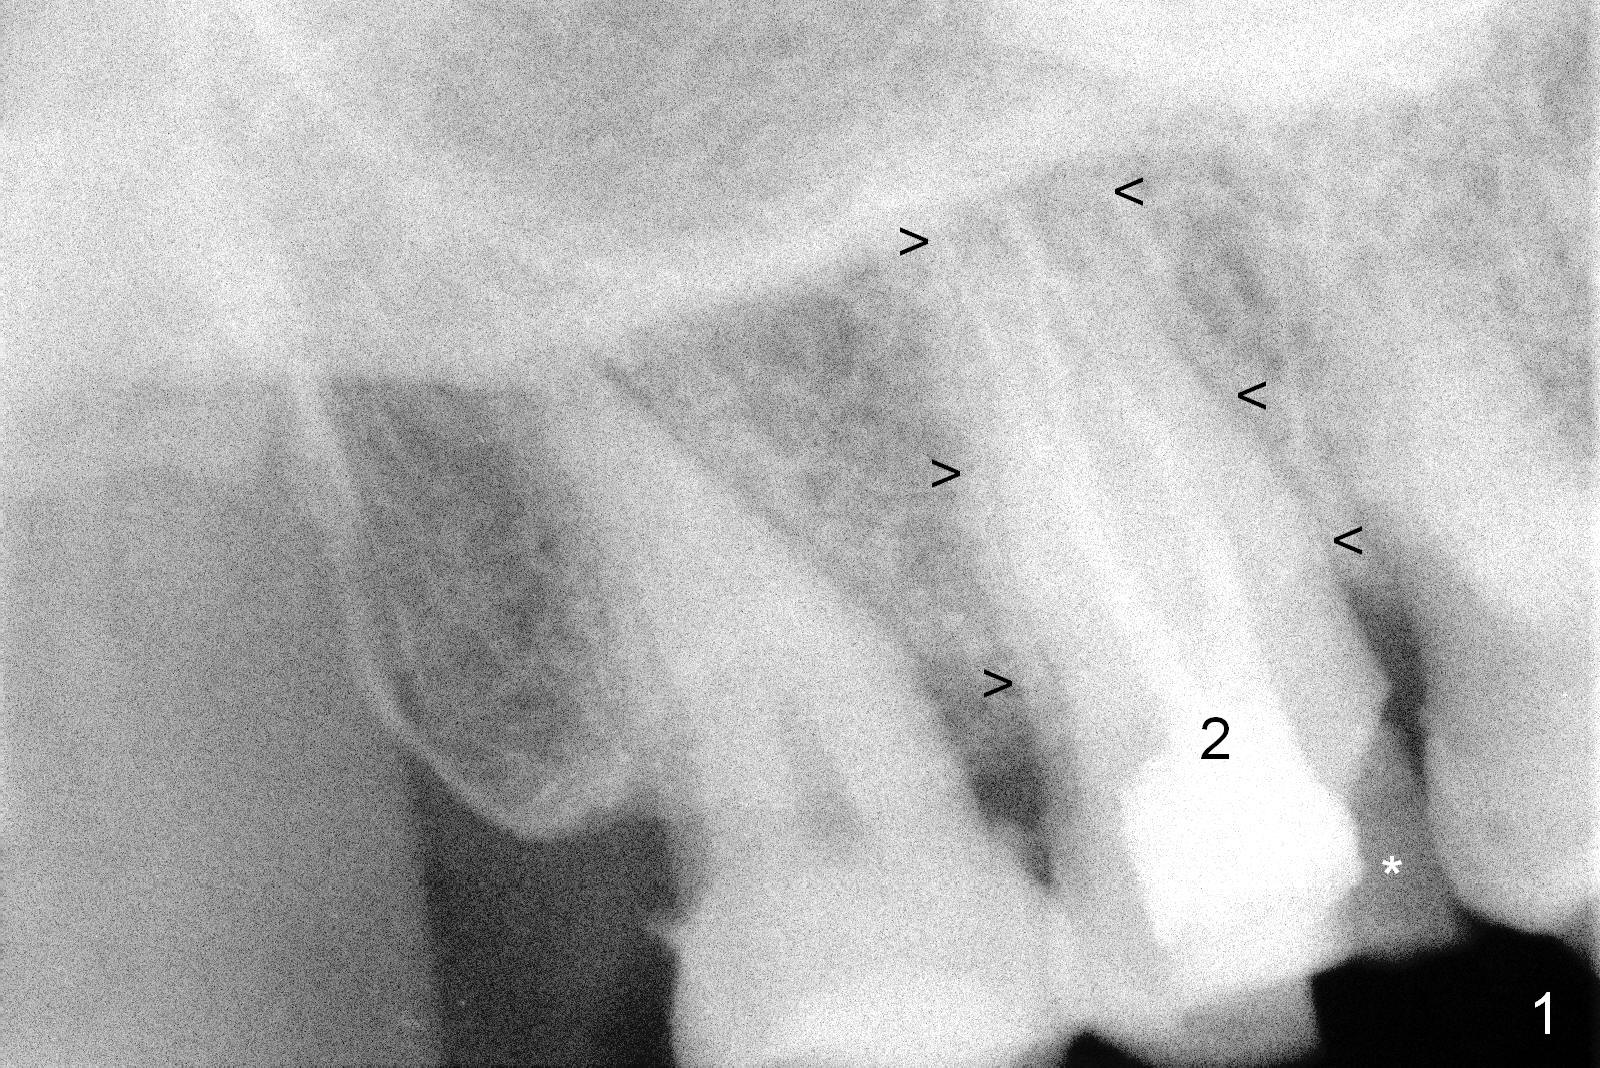

A 65-year-old lady is at early stage of Parkinson's disease and appears to be a bruxer. There are multiple chipped teeth, including #2 (Fig.1,4 *). She chooses implant over RCT retreat. A tissue-level implant (Fig.2) matches the root shape of the affected tooth better than a bone-level one (Fig.3), because of taper. The buccopalatal and mesiodistal dimensions of the extraction socket are 11 and 8 mm, respectively (Fig.5,7).

The buccal roots are fused. The buccal socket (BS) seems to be larger than the palatal one (PS). There is a septum (S) between the 2 sockets. Both the buccal and palatal plates (BP, PP) are intact. The anatomy is illustrated in Fig.6a (buccopalatal section) with the same abbreviations, mentioned above. SF: sinus floor.

Osteotomy for immediate implant is initiated with a 2 mm pilot drill (Fig.6b red arrow) in the coronal end of the buccal slope of the septum (center of the socket). Once the drill gets initial penetration, the trajectory changes to the long axis of the tooth (Fig.6c). Then PA is taken with a parallel pin (Fig.7). It appears that the depth is not enough; there is bone apical to the pin. As osteotomy increases in diameter, burs may be deviated buccally due to the septal buccal slope (to be discussed below). With longer osteotomy, the deviation may be less. Osteotomy is deepened (Fig.6d). From this moment on, nose blowing test is done after each step. The result is all negative. As drill diameter increases, they do deviate buccally (Fig.6e arrow), since there is less bone contact buccally than lingually (compare Fig.6e,f). With the same reason, smaller tapered taps (Fig.6g pink, 5 and 6 mm) tend to be mobile buccally (arrow). When a large tap (7 mm) is inserted (Fig.8), there is no buccal mobility. It appears that the tap contacts more of the buccal plate (Fig.6h), but the coronal end of the tap is buccal (Fig.6i, pink circle). At each step of osteotomy, the coronal end of a bur or tap should be pushed as lingual as possible so that the final tap is favorable for restoration (Fig.6j). Sinus lift is done (Fig.6k red circle; Fig.9 *) before placement of 7x17 mm implant (I, >60 Ncm). Since the palatal socket is not associated with implant stability, it is closed by collagen plug (Fig.6l, blue area). As extra precaution, bone graft is placed around the coronal portion of the tissue-level implant (Fig.6l red circles), followed by collagen dressing.